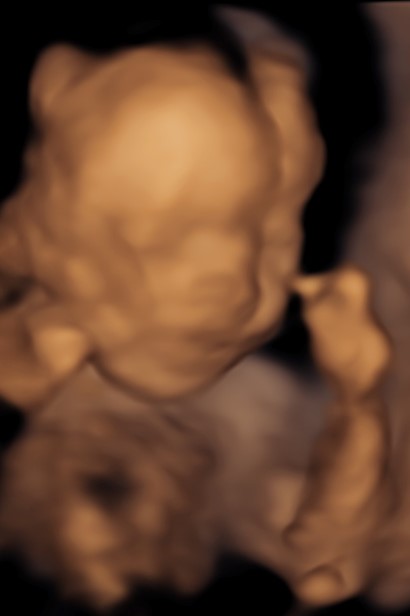

4D/5D/HD Ultrasound Gallery

Gallery